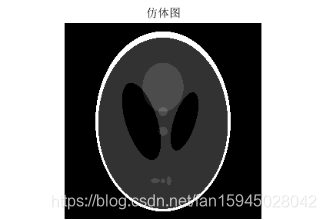

5.3.2模型建立与求解

误差以及原因已经分析完,下面自行建立一个模版对本模型进行检验和阐述,利用matlab函数自动获取一个头骨图形仿体,对仿体的灰度像素矩阵进行拆分,拆分成本题附件所给CT扫瞄的接受数据形式,然后再行图形重建,先利用原来未滤波的模型再进行滤波模型重建,程序见附录程序五,结果如下图:

图 17

图 18

图 19